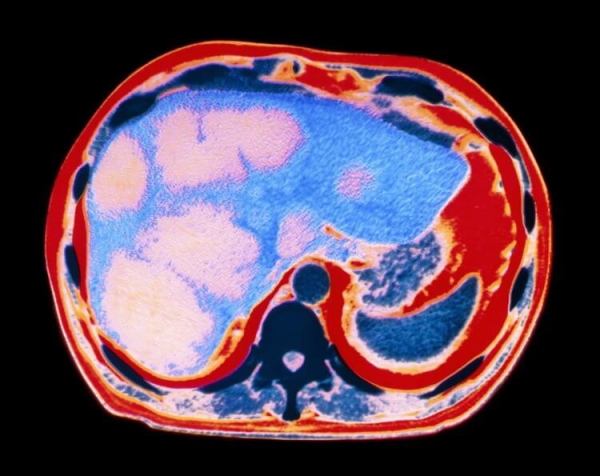

Напомним, что при потреблении алкоголя человеческий организм превращает его в ацетальдегид – вещество, способное вызывать окислительный стресс, что приводит к нарушению функций печени и способствует накоплению в организме уксусной кислоты. Отметим, что основной механизм повреждения печени связан с развитием жировой болезни, алкогольного гепатита и цирроза (основные факторы риска для развития рака печени).

Главным выводом новой работы стала выявленная взаимосвязь между употреблением алкоголя и раком головы и шеи, раком пищевода, раком печени, раком желудка, раком толстого кишечника и раком молочной железы. Исследователи также отметили, что сочетание употребления алкоголя с курением значительно увеличивает риск развития онкологии.